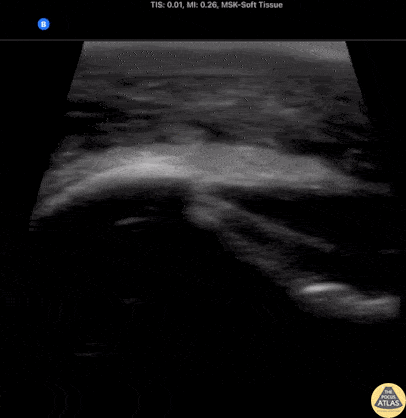

Soft Tissue - Deep Cellulitis with Phlegmon

20s M with PMH IVDU presented with R elbow wound for a few days. On exam, there was a focal wound with purulence near the R elbow with extensive erythema, induration, and tenderness to the R forearm and distal upper arm. The patient was hemodynamically stable. Labs were concerning for a markedly elevated white blood cell count and CRP. Given the clinical concern for necrotizing soft tissue infection (NSTI), POCUS was performed of the affected area. Shown here, the POCUS demonstrates extensive cobblestoning with fluid seen along the fascial planes superficial to the muscle. Orthopedic surgery was consulted with concern for NSTI, and performed a bedside I&D which did not suggest NSTI, and the patient was admitted for IV antibiotics and management of the severe cellulitis. Dr. Nhu-Nguyen Le, Ultrasound Fellow Denver Health Ultrasound Fellowship